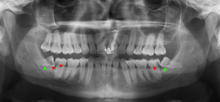

Wisdom teeth likely become impacted because of a mismatch between the size of the teeth and the size of the jaw. Impacted wisdom teeth are classified by their direction of impaction, their depth compared to the biting surface of adjacent teeth and the amount of the tooth's crown that extends through gum tissue or bone. Impacted wisdom teeth can also be classified by the presence or absence of symptoms and disease. Screening for the presence of wisdom teeth often begins in late adolescence when a partially developed tooth may become impacted. Screening commonly includes clinical examination as well as x-rays such as panoramic radiographs.

If the tooth cannot be assessed with clinical exam alone, the diagnosis is made using either a panoramic radiograph or cone-beam CT. Where unerupted wisdom teeth still have eruption potential several predictors are used to determine the chance of the teeth becoming impacted. The ratio of space between the tooth crown length and the amount of space available, the angle of the teeth compared to the other teeth are the two most commonly used predictors, with the space ratio being the most accurate. Despite the capacity for movement into early adulthood, the likelihood that the tooth will become impacted can be predicted when the ratio of space available to the length of the crown of the tooth is under 1.[3]:141